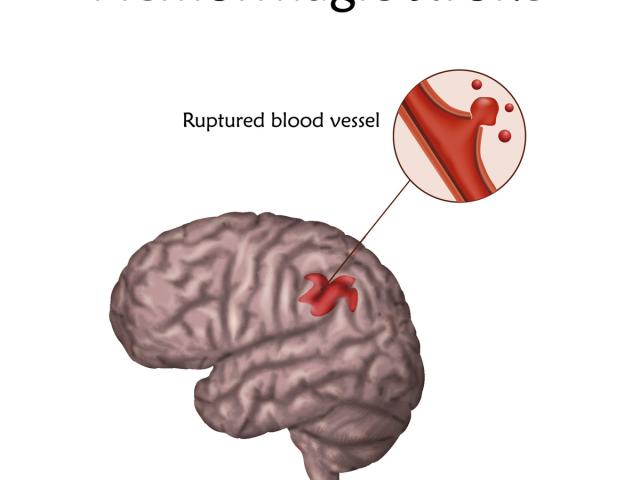

La hipertensión es una condición médica que aumenta el riesgo de padecer enfermedades cardíacas, cerebrales y renales.